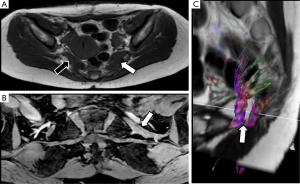

The sciatic nerve is the major PN in the body, both for its length and its width. Clinical manifestations of sciatic nerve are common, and are challenging to study with MRI due to its length. Sciatic nerve entrapment usually occurs at a pelvic level, the so-called piriformis syndrome, due to a mass compression, trauma or a compression neuropathy (68,69). According to some authors, the existence of a piriformis hypertrophy, as may occur in runners, or accessory muscle can condition compression on the sciatic nerve and justify the symptoms (70,71). Morphological MRI is able to determine the anatomy of the piriformis muscle and its relation with the sciatic nerve, bur may not always show enough accuracy for detecting changes at the sciatic nerve that justify the symptoms. However, DWN allows multiplanar reconstructions that facilitate the qualitative assessment of the nerve in almost its entire length, detecting differences in signal intensity of the sciatic nerve in comparison to the contralateral, healthy one (Figure 13). Furthermore, at the point of nerve compression, ADC shows higher values than in the rest of the nerve, presumably due to the coexistence of edema (40,72). 3D neurographic reconstructions from DTN data may help in the assessment of the relationship between sciatic nerve and piriformis muscle and its several variants that may help clinicians to establish a most certain diagnosis of this underdiagnosed entity (73) (Figure 14).

DTI has the added value to perform 3D reconstructions of PN. For PN injuries, 3D neurographic reconstructions may represent the structure of the damaged nerve. This representation may be useful for surgeons for treatment planning and assessment of the relationship of PN with neighboring structures (Figure 7). In cases of severe PN damage, a decrease of FA values under the determined threshold in the software for its 3D representation, may lead to an underestimation of its structure (40).